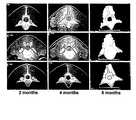

FIGS. 1 and 2 depict a digitized images of computerized tomography (CT) scans of an L4-L5 posterolateral spinal fusions performed on rhesus monkeys as described in Example 5 (top panels, section through superior transverse processes; middle panels, section through disc space; lower panels, section through inferior transverse processes).

The fusions were also evaluated by CT scan at 2, 4 and 6 months after implantation.FIGS. 1 and 2 show the CT scans for each subject studied.FIGS. 1 and 2 demonstrate the sequence of events that occur within the composite sponge carrier loaded with rhBMP-2. On the far left of the figures are three CT sections equally spaced throughout the fusion mass at 2 months post-operative, showing that resorption of the composite sponge is just about complete due to the lack of radiopacity of the ceramic granules. The three middle CT sections show these same three CT sections at four months with increased bone deposition where the carrier once resided. The composite sponge has maintained the space within the soft tissue site for a sufficient enough period of time for the desired volume of new bone deposition to occur. Finally, the far right three CT scans show even further bone deposition, remodeling and maturation with the formation of outer cortices around the periphery of the fusion masses by six months.